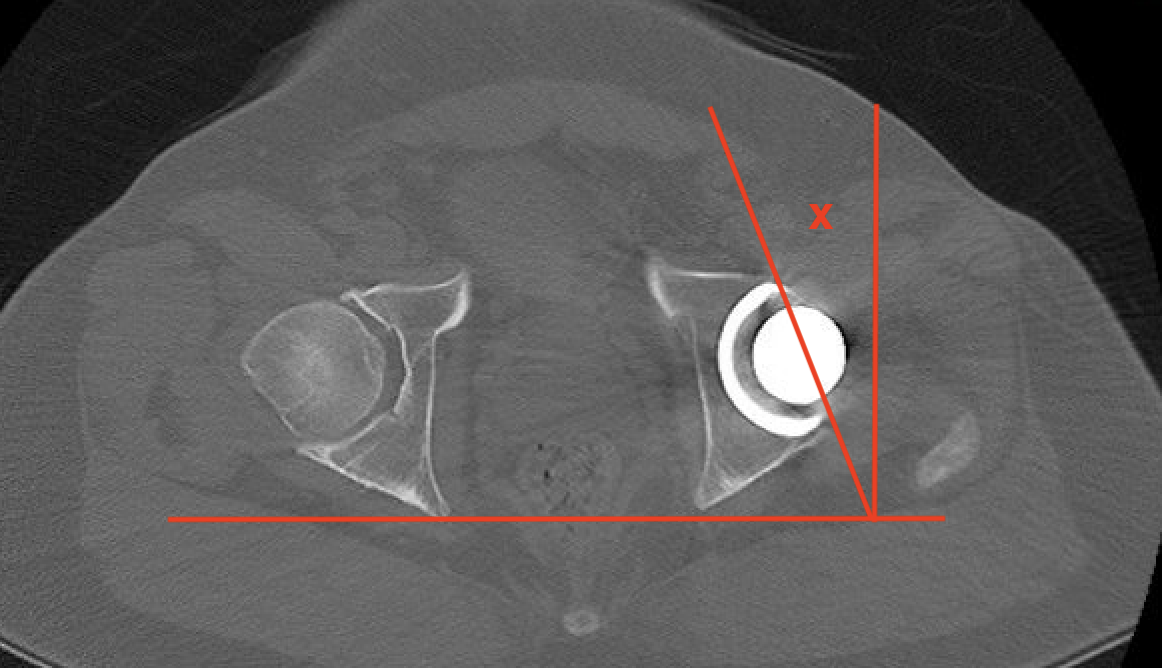

3. Femoral Version

CT scan

- line prosthesis neck

- line posterior femoral condyles